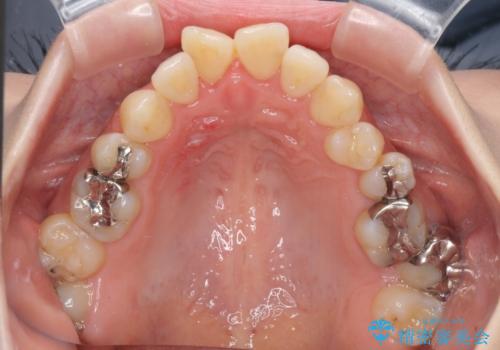

- 奥歯のむし歯を気にして来院された患者様です。

当初は右下の虫歯治療のみを希望されていましたが、虫歯治療に際して部分矯正が必要であったため、治療方法について説明をすると、全体的に歯列不正が気になっているとのことで、全顎矯正を検討することとなりました。

口元の突出感とデコボコがあり、上下左右の小臼歯4本を抜歯して矯正治療を行う方針としました。(右上は欠損のため計3本抜歯)

むし歯となっている歯は状態が悪く、将来的に抜歯となる可能性が高かったため、定石で抜歯させる小臼歯の代わりにむし歯となっている大臼歯を抜歯し、ワイヤー装置にて矯正治療を行うこととしました。